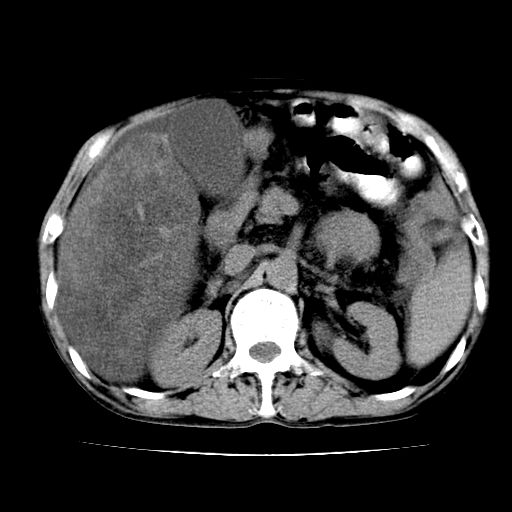

男,55岁,发现“肝硬化”5年,现腰疼、腹胀10余日,巩膜黄染、腹稍胀,肝肋下3指,质硬无压疼,移动性+,血生化:总胆、直胆、间胆均升高。

g1:肝硬化、脾大、腹水。

2:脂肪肝。

3:弥漫性肝癌待排。

肝硬化,脾大,腹水

脂肪肝

肝内多发低密度灶(建议增强扫描除外肝癌)

肝脾肿大,脂肪肝,腹水。建议增强除外肝癌。